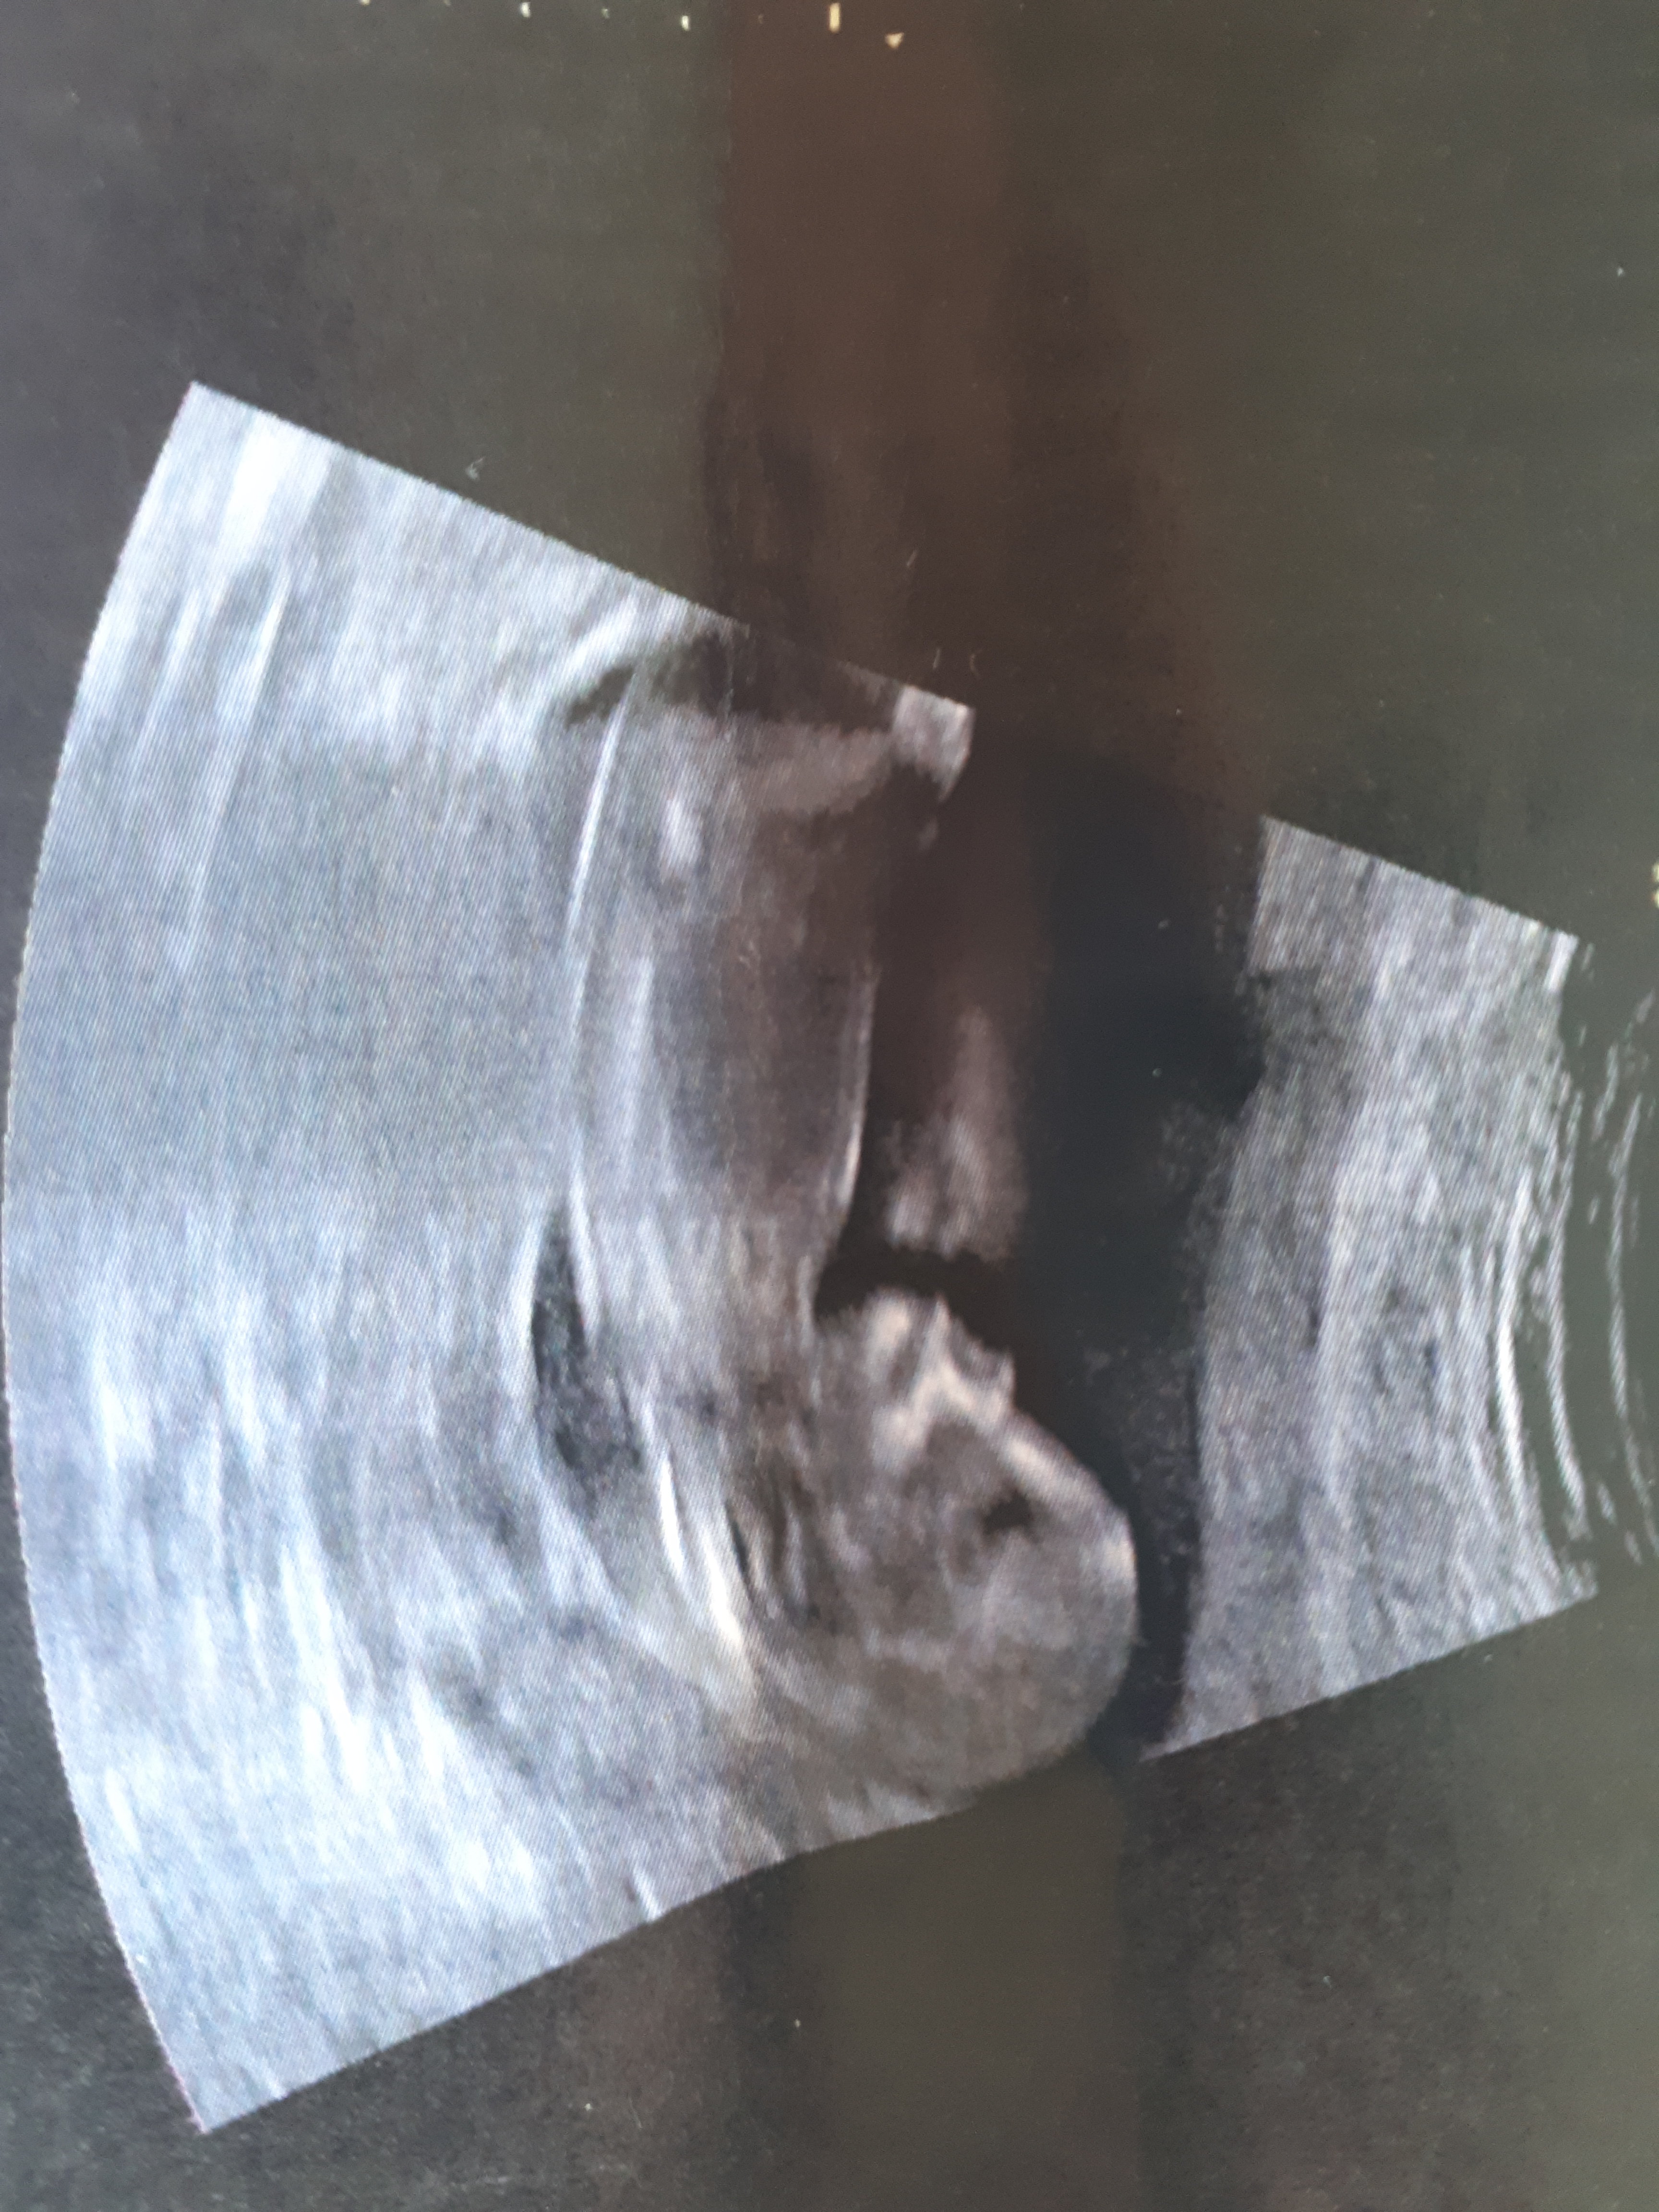

Hej jestem już po badaniach prenatalnych wszystko ok 3 razy wychodziłam bo dziecko zle było ulozone zresztą lekarz mnie uprzedził że to badanie trwa 3min,3godz lub 3dni w zależności od możliwości podgladowych jestem spokojniejsza bo wszystko jest w normie krew pobrali wyniki za 2 tyg ale wg usg póki co wszystko w normie i tak

Jestem 13/4 Dziś A dzidzia ma już 7cm .